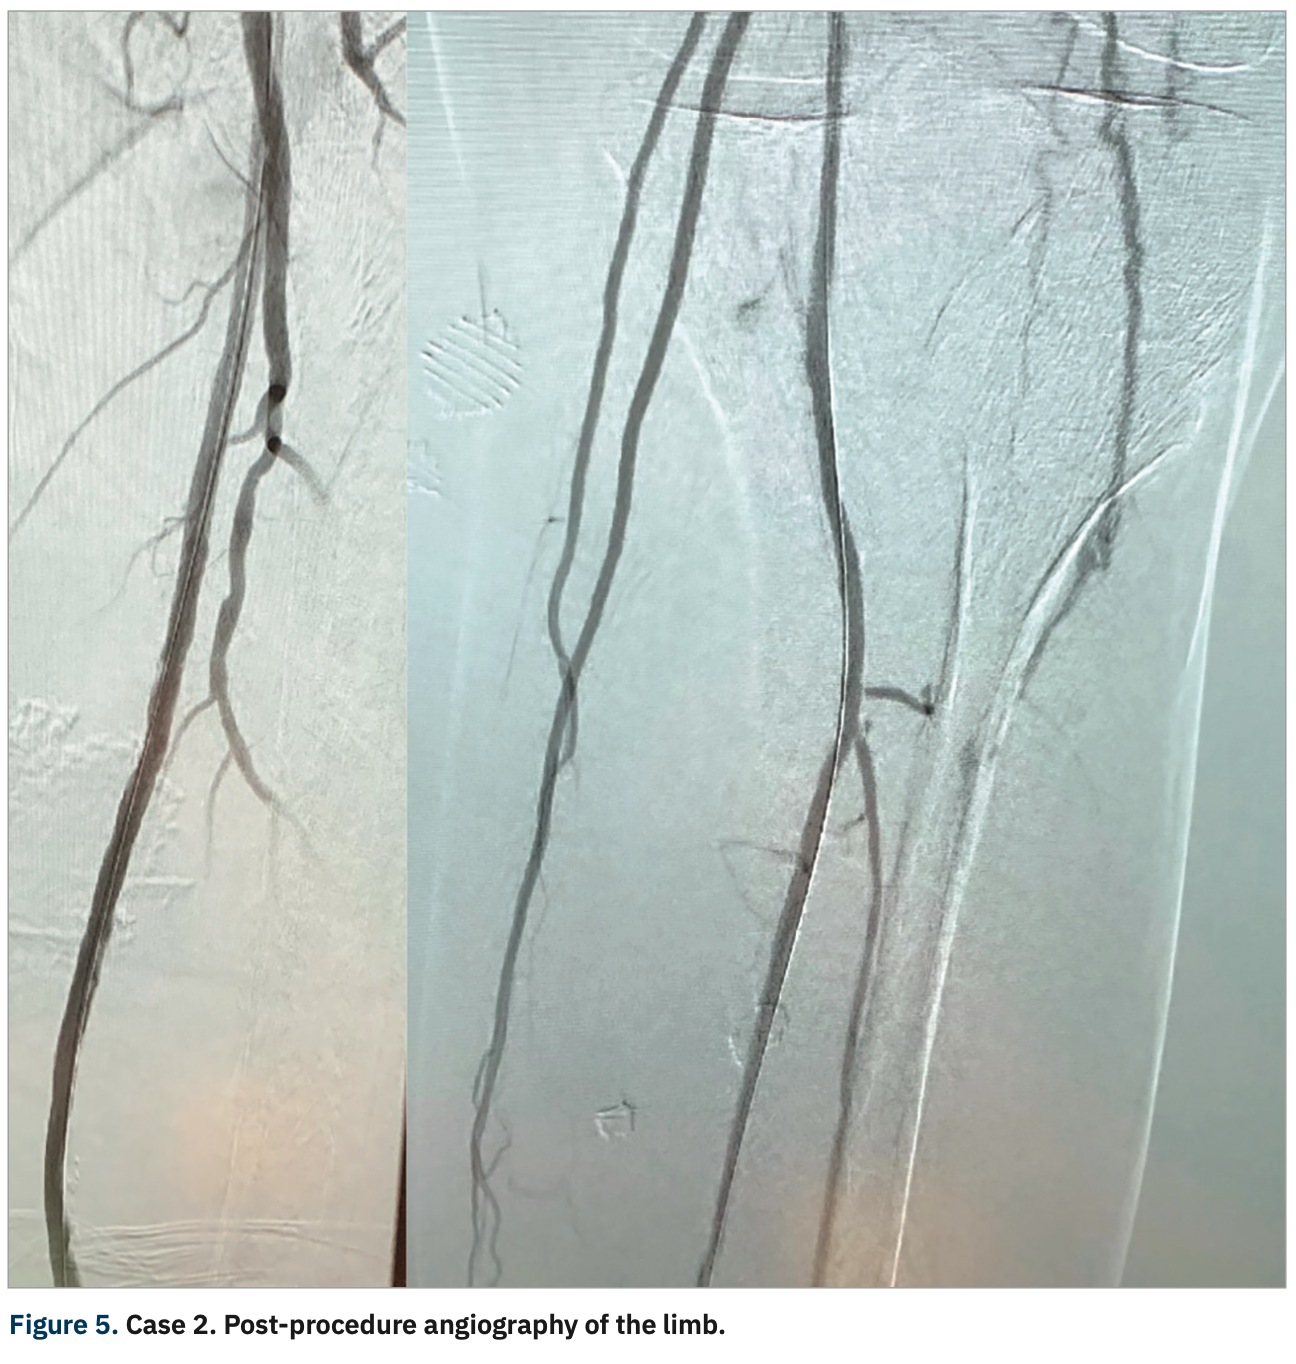

Post-procedure angiography (Figure 2) showed a widely patent SFA with no residual stenosis extending into the above-knee popliteal artery with a maintained trifurcation and 3-vessel runoff to the right foot. The patient was discharged and his right foot ulcer proceeded to heal. He no longer has right leg pain.